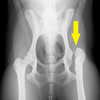

• 猫の骨盤骨折

2020.2.23

1歳 雄猫

稟告/倒れていた猫を保護